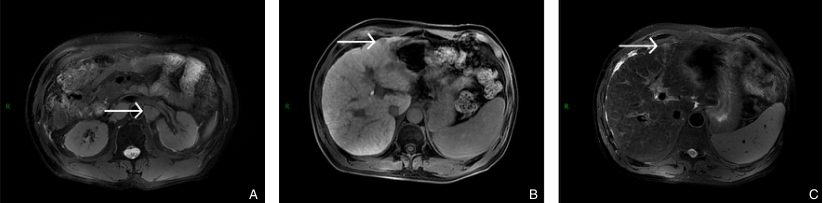

图7 2024年11月患者术后复查MRI A-B:病变在T1加权成像(T1WI)中呈稍低信号,在T2加权成像(T2WI)中呈高信号;C:可见复发淋巴结Fig.7